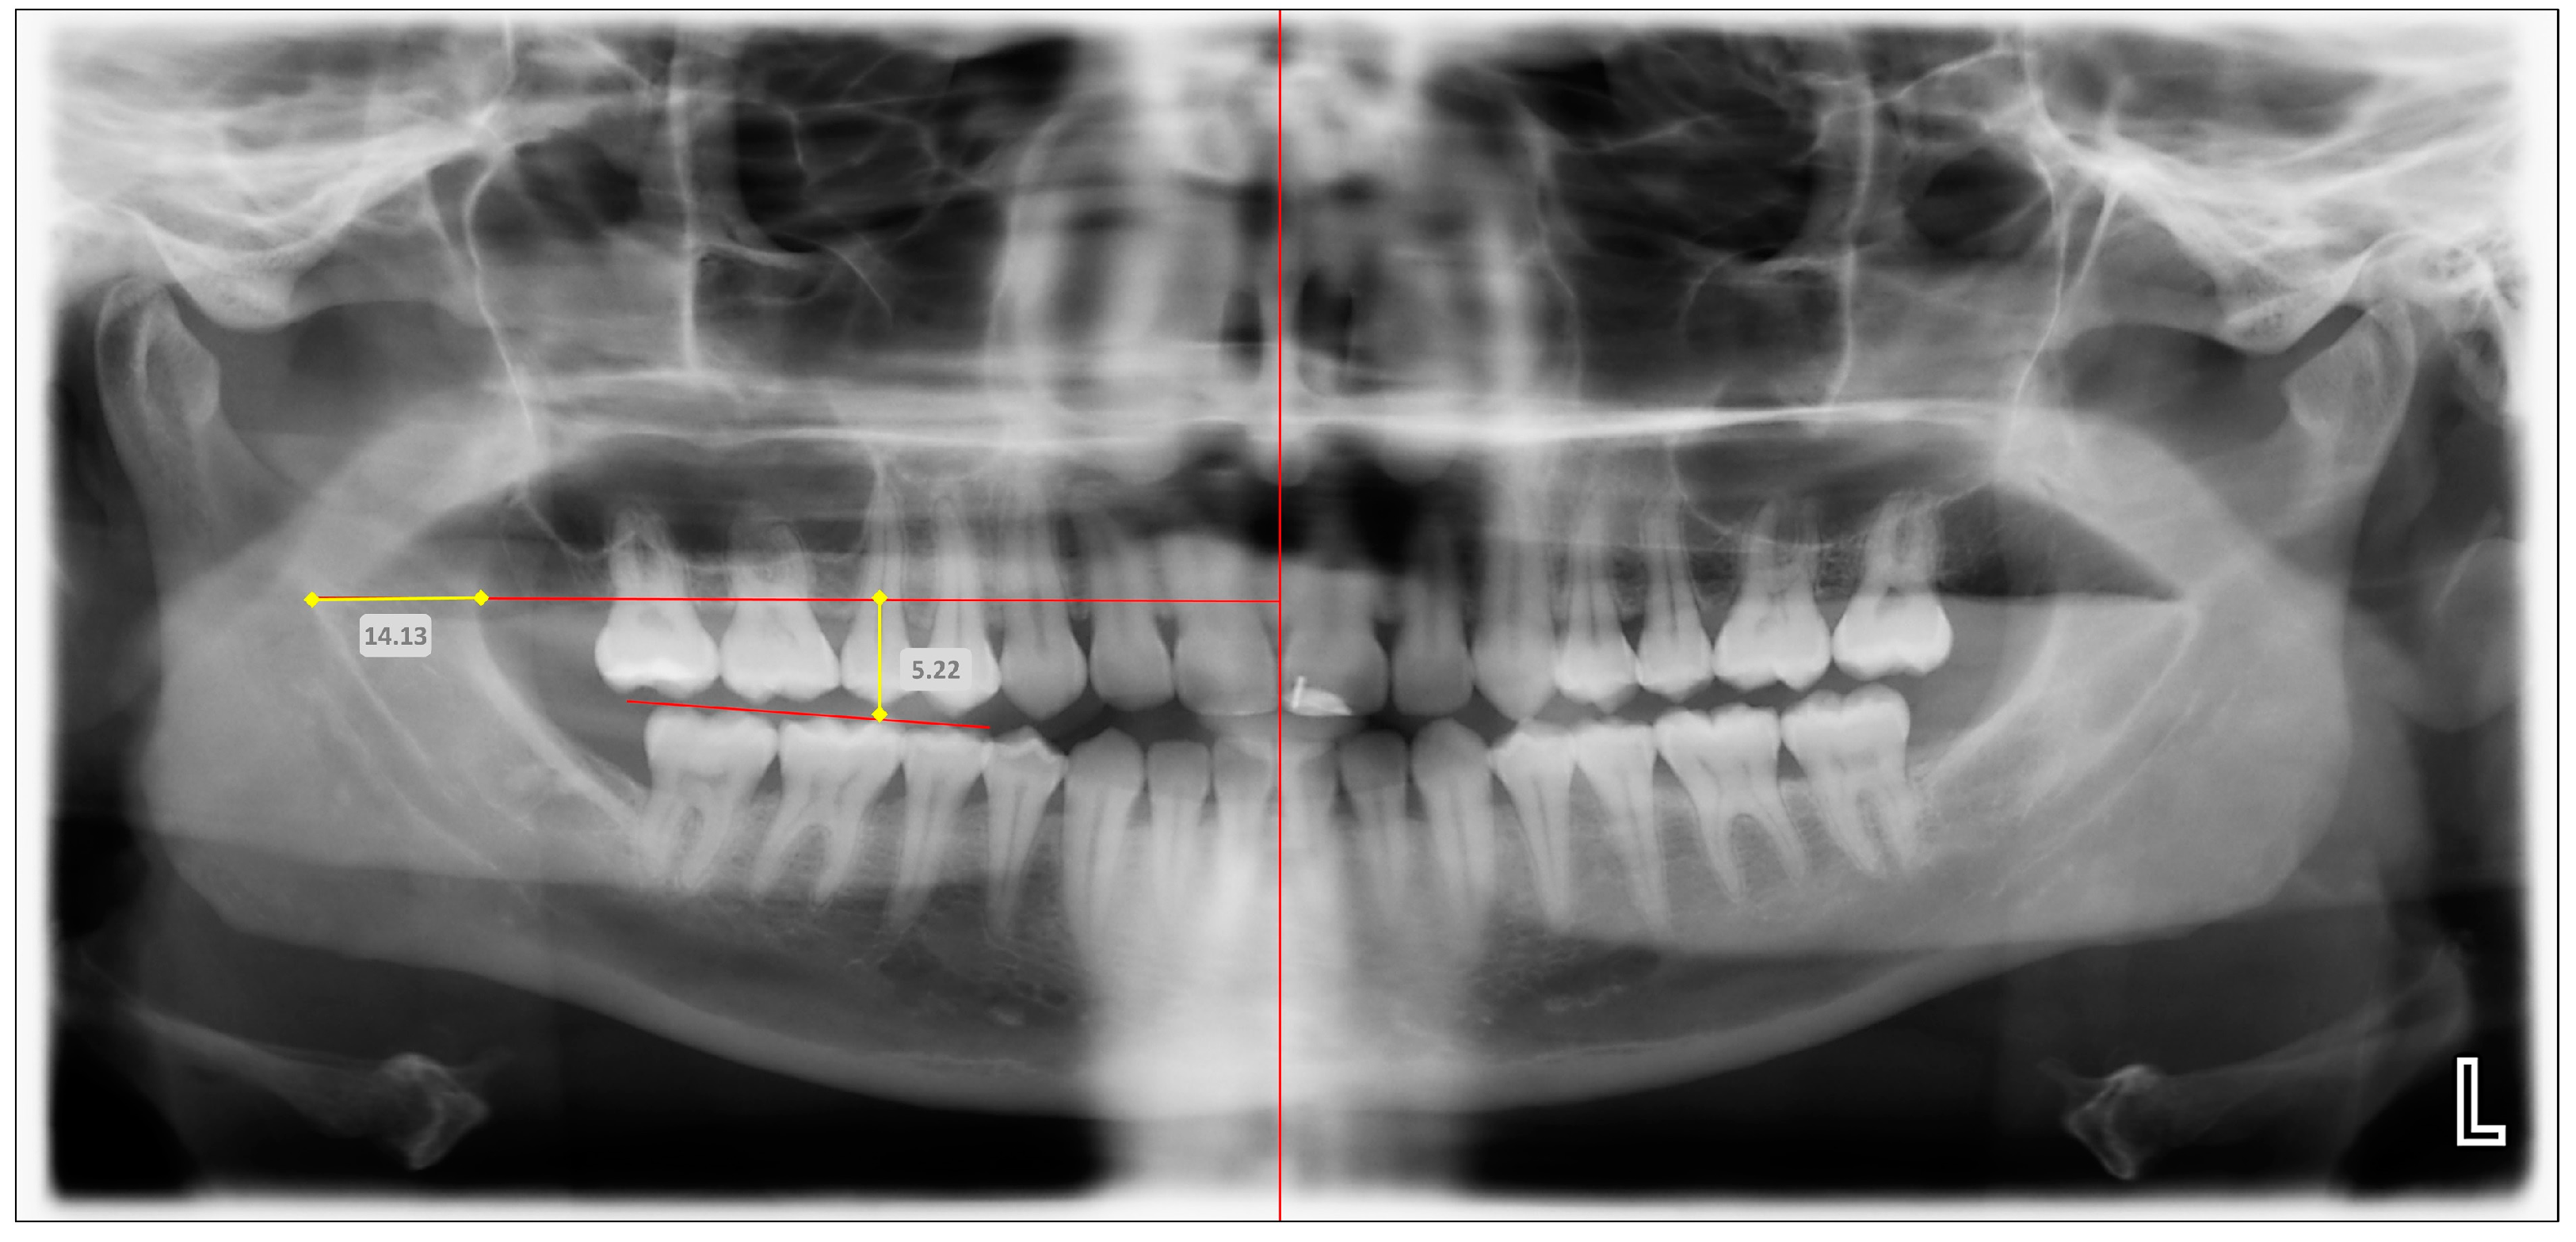

| Variable | Description | Radiographic Technique | Abbreviation Based on Anatomic Localization | |

|---|---|---|---|---|

| Right | Left | |||

| Anteroposterior position of mandibular foramen | Horizontal distance from anteroinferior border of mandibular foramen to anterior border of mandibular ramus | OPG | MF-AP-OPG (Right) | MF-AP-OPG (Left) |

| CBCT | MF-AP-CBCT (Right) | MF-AP-CBCT (Left) | ||

| Superoinferior position of mandibular foramen | Vertical distance from anteroinferior border of mandibular foramen to mandibular occlusal plane (at level of mesial cusp of first molar) | OPG | MF-SI-OPG (Right) | MF-SI-OPG (Left) |

| CBCT | MF-SI-CBCT (Right) | MF-SI-CBCT (Left) | ||

| Anteroposterior position | Right | 13.53 ± 2.44 (7.1–20.2) | 13.61 ± 2.39 (7.8–19.6) | 0.335 | 0.738 | 0.942 |

| Left | 13.19 ± 2.25 (7.7–18.1) | 13.36 ± 2.19 (8.1–18.8) | 0.773 | 0.439 | 0.903 | |

| Superoinferior position | Right | 5.25 ± 1.71 (4.2–6.2) | 5.59 ± 1.66 (4.5–6.6) | 2.038 | 0.042 | 0.939 |

| Left | 5.41 ± 1.65 (4.1–6.3) | 5.52 ± 1.61 (4.6–6.5) | 0.682 | 0.496 | 0.912 | |